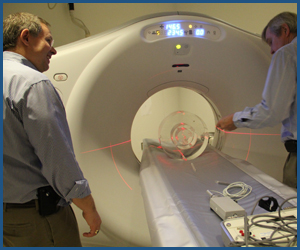

QC-Track Module:

CT

The QC-Track module for CT QC meets the needs of the most widely followed regulations in CT quality control,

including the ACR Continuous Quality Control Program per their "CT Accreditation Program Requirements" and The Joint

Commission "Diagnostic Imaging Requirements," as well as CT vendor QC programs.